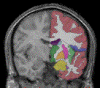

Online resource for validation of brain segmentation methods. posted by NITRC Moderator on Sep 21, 2019